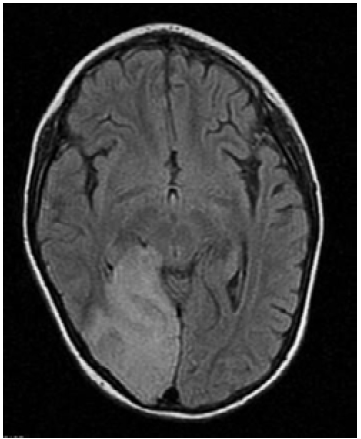

Seis meses después, la paciente presentó deterioro neurológico progresivo, disminución de la fuerza muscular, persistencia de la marcha atáxica, mutismo y falta de seguimiento visual. La TAC de cráneo de control evidenció lesión sugestiva de infarto cerebral en el lóbulo occipital derecho y la RMN en T1 mostró hipointensidad cortico-subcortical temporo-occipital derecha con leve efecto compresivo sobre la línea media y el cuerno occipital del ventrículo lateral ipsilateral (Figura 1), por lo que se sospechó diagnóstico de síndrome MELAS. Se obtuvieron diferentes trazados espectrales del parénquima sano que se correlacionaron con los resultados de la RMN, lo cual permitió observar una disminución en los picos de N acetil aspartato, colina y creatina, y la aparición de pico dominante de lactato cerebral.

En las neuroimágenes de pacientes con síndrome MELAS se pueden encontrar lesiones cerebrales similares a un infarto cerebral isquémico -especialmente en las regiones posteriores de los lóbulos temporales, parietales y occipitales- pero que superan un territorio vascular; de igual forma, son evidentes las calcificaciones cerebrales en ganglios basales y la atrofia cerebral desproporcionada para la edad del paciente,9 tal como se corroboró en el caso descrito (Figura 2).